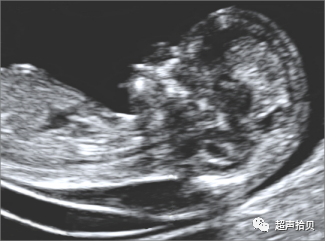

5-2)意义

尽管NT增加与胎儿畸形和胎儿死亡相关,绝大多数NT增加的胎儿其妊娠结局仍是活产健康新生儿,而且发育正常。

• 发现NT增厚以后,必须尽可能快速和准确地区分哪些胎儿是正常的,哪些胎儿异常。